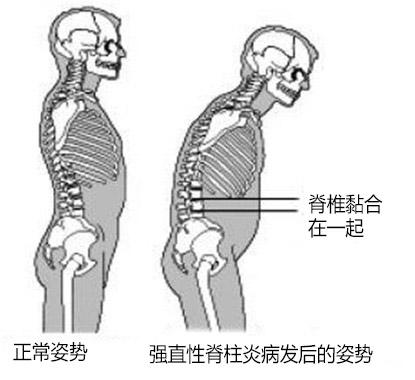

强直性脊柱炎以骶髂关节和脊柱附着点炎症为主要症状的疾病。与HL ...

强直性脊柱炎,是一种原因不明的、以中轴关节慢性炎症为主的全身 ...